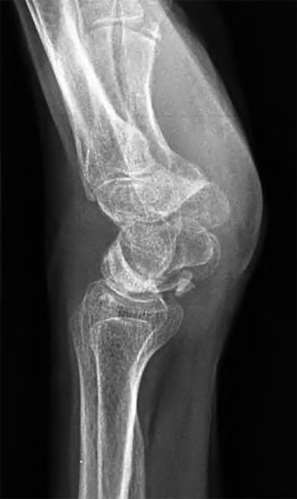

A 35-year-old woman reports wrist pain after a fall onto an outstretched hand. On exam, she has focal tenderness over the wrist snuffbox. A radiograph and CT image are shown in Figures A and B. What is the proper treatment of her injury?